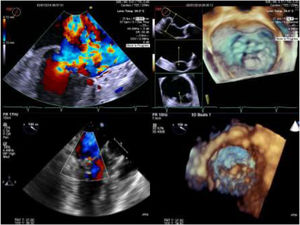

Intra-operative two dimensional and three-dimensional TEE were routinely used to guide neochordae navigation, attachment, and adequate tensioning.10Figure 1 shows an example of intraprocedural TEE result. All patients had a comprehensive transthoracic echocardiographic evaluation by the time of discharge, and between three to six months follow-up.

Two and three-dimensional transesophageal echocardiogram is essential for off-pump transapical neochord implantation planning and real-time guiding. Left upper panel: baseline severe mitral regurgitation jet, eccentrically oriented toward interatrial septum, due to posterior leaflet prolapse. Right upper panel: Surgical view of mitral valve from an atrial perspective, showing P2 prolapse (arrow). Left lower panel: Mild grade mitral regurgitation after two neochordae implantation. Right lower panel: Three-dimensional view of mitral valve following neochordae implantation confirmed correction of P2 prolapse.